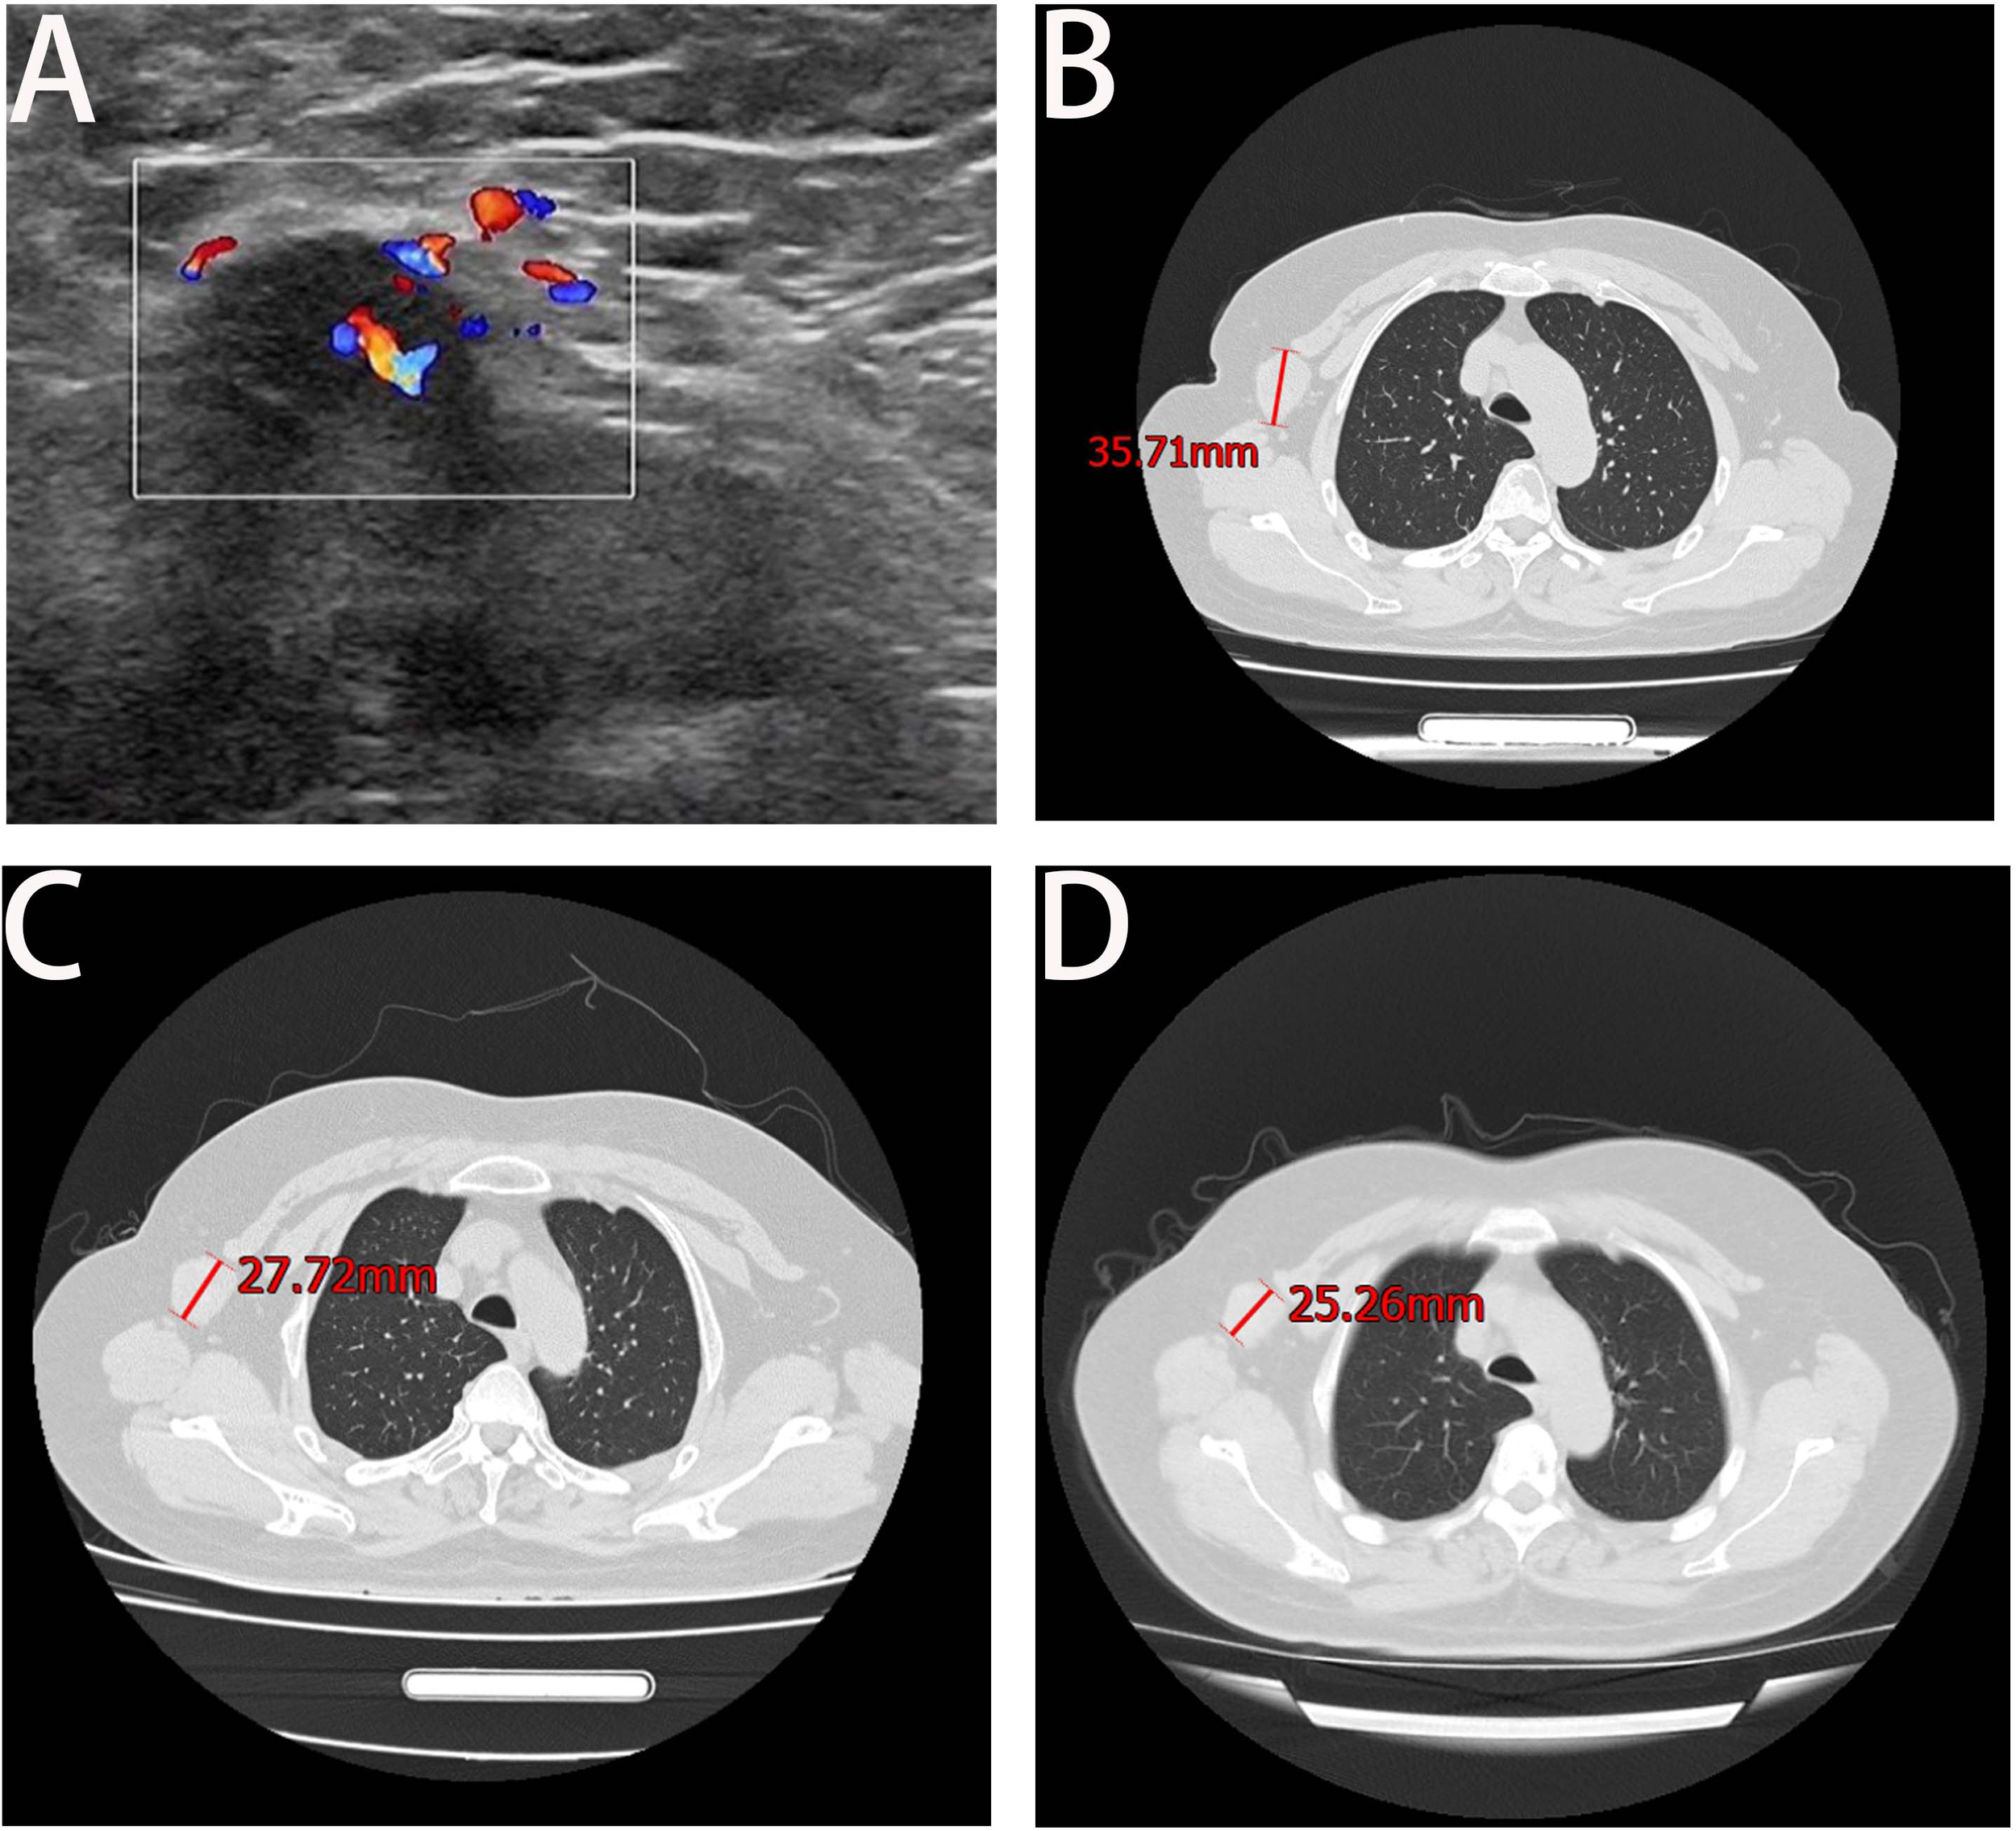

A 68-year-old female patient presented at our hospital on 28 May 2023, with a chief complaint of “low back pain with left lower limb pain for 2 weeks.” Upon specialized physical examination, she exhibited a normal gait upon entering the ward. The patients reported left lumbar back pressure pain without radiation to the lower limb. Examination of the lumbar spine indicated normal flexion and extension activity, with left quadriceps muscle strength graded at level IV. Sensation in the lower limbs and saddle area was intact, alongside normal muscle tension. Bilateral heel–knee tendon reflexes were within normal limits, with no pathological signs detected. Normal skin temperature and color were normal in the right axilla. Palpitation revealed soft masses approximately 5 cm × 3 cm in depth, with indistinct boundaries, absence of tenderness, and immobility. Subsequent lumbar spine X-ray depicted slight flattening of the lumbar vertebra 4 (L4) vertebral body (Figure 1A). Computed tomographic (CT) imaging of the lumbar spine revealed flattening of the L4 vertebral body, thin and discontinuous bone cortex, and osteolytic bone destruction on the left side of the vertebra, measuring approximately 3.0 cm × 2.0 cm × 2.2 cm (Figure 1B). No compression of the dural sac or significant abnormalities in the surrounding soft tissue were noted. Lung CT revealed distinctive insect-like patterns of local bone destruction affecting thoracic vertebra 4 (T4) and the right first rib, with irregular soft tissue density shadows observed in the right armpit (Figure 2B). Lumbar magnetic resonance imaging (MRI) displayed an uneven bone damage signal in the L4 vertebral body (Figure 1E). Ultrasonography detected a low-echo mass measuring approximately 32 mm × 26 mm, featuring clear boundaries and an irregular shape, exhibiting uneven internal echoes and the characteristic “rat tail sign” at both ends in the right axilla (Figure 2A). Emission computed tomography (ECT) scans revealed multiple abnormal focal nuclide concentrations in the right first rib, L4 vertebral body, and right iliac bone, consistent with bone metastases (Figure 3). To determine the nature and origin of the tumors, a CT-guided puncture biopsy of the right iliac bone tumor was conducted on 29 May 2023, revealing a short spindle-cell malignant mesenchymal tumor suggestive of MPNST upon immunohistochemistry and staining (Figure 4A). Subsequently, on 6 June 2023, an ultrasound-guided puncture biopsy of the right axillary soft tissue tumor confirmed MPNST (Figure 4B). The final diagnosis was MPNST with multiple metastases.

Figure 2

Axillary ultrasound and lung CT. Panel (A) shows the right axillary probe and irregularly shaped hypoechoic mass, measuring approximately 32 mm × 26 mm. Panel (B) shows the maximum axillary mass diameter at the time of initial admission. Panel (C) shows a significant reduction in the maximum diameter of the irregular soft tissue mass under the right axilla at the end of the entire chemotherapy cycle. Panel (D) displays the result of the February 2024 review, which indicated a decrease of approximately 2 cm in the maximum tumor diameter from the previous review.

Following thorough departmental deliberation, initiation of a chemotherapy regimen combining cisplatin with doxorubicin was decided upon. Given the predominant imaging findings of osteolytic bone destruction, denosumab, FDA-approved for preventing skeletal-related events in patients with bone metastasis from solid tumors, was adjunctively administered to inhibit osteolysis. The treatment protocol combined chemotherapy (AP regimen cisplatin (DDP) 120mg/m2/day ×1 day + pegylated liposomal doxorubicin (PLD) 40 mg/m2/day × 1 day, once every 21 days) with denosumab (120 mg, subcutaneous injection, once/4 weeks), supplemented with Vitamin D3 (600 μg daily). Throughout the treatment course, the patient experienced significant alleviation of pain symptoms compared to admission, improved sleep without medication assistance, and absence of drug-related adverse reactions. Regular imaging assessments performed before each admission facilitated the evaluation of the combination therapy’s efficacy. Following the completion of six cycles of chemotherapy, pulmonary CT scans evidenced a gradual reduction in the maximum diameter of the irregular soft tissue mass under the right axilla (Figure 2C), while lumbar spine CT exhibited thickening and densification of the bone cortex surrounding the L4 vertebral body, accompanied by evident bone formation and scattered calcification shadows in the area of osteolytic bone destruction (Figure 1C).

On 18 October 2023, the patient completed six cycles of chemotherapy combined with denosumab treatment, with lung CT indicating an absence of lung metastasis. Evaluation of the soft tissue mass in the right armpit, designated as the target lesion according to RECIST 1.1 criteria, revealed stable disease. To inhibit disease progression post-cessation of intensive chemotherapy cycles, the patient was prescribed the oral targeted drug anlotinib (12 mg/day, taken for 2 weeks followed by a 1-week break) to enhance chemotherapy sensitization and prevent disease progression. Denosumab (120 mg, subcutaneous injection, once every 4 weeks) was continued to enhance bone strength. Presently, the patient has endured the tumor for 10 months. Regular follow-up visits every 3 months for lung and lumbar CT scans were advised to monitor therapeutic efficacy and adjust the medication regimen as necessary. On 20 February 2024, a re-examination CT revealed prominent calcification in the area of bone destruction in the L4 vertebral body (Figure 1D), with no significant alteration in the maximum diameter of the axillary mass compared to the previous scan (Figure 2D).